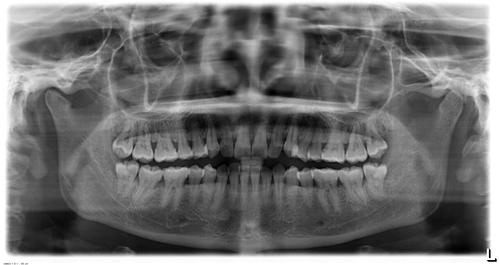

智齿拍片

智齿x光片

阻生智齿

阻生智齿图片